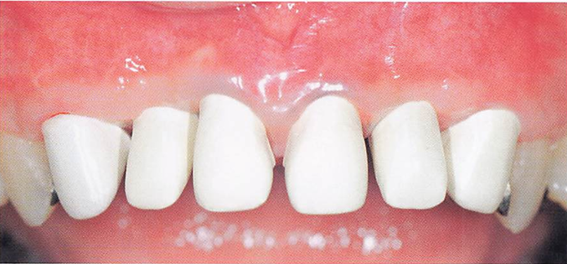

午前-39

43歳の男性。上顎前歯の変色を主訴として来院した。小学生の頃から縞模様が気になっていたという。初診時の口腔内写真を別に示す。 考えられる変色の原因はどれか。1つ選べ。

a.歯髄の失活

b.フッ化物の過剰接種

c.コーヒー飲料品の色素成分の付着

d.テトラサイクリン系抗菌薬の長期服用

解答を見る

d